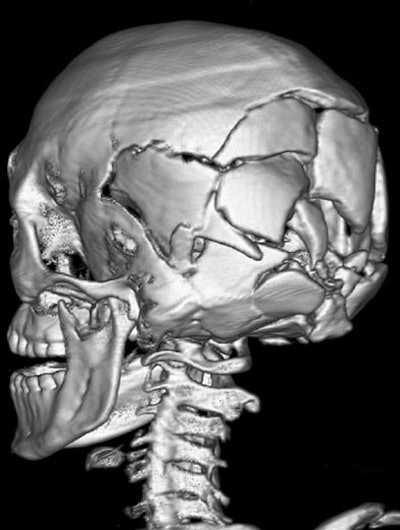

| Features of a gunshot wound to the head at virtual autopsy. Top and below, transverse CT images of a lethal gunshot wound to the head show multiple calvarial fractures, posterior settling of the brain, and pneumocephalus. Metallic fragments and foci of gas are present in the left cerebellum (below). A distinct linear bullet track is not present. Bottom, 3D volume-rendered image of the skull shows the comminuted fracture of the posterior skull. Republished with permission of the Radiological Society of North America from Radiology (August 2006, Vol. 240:2, pp. 522-528); published online before print as 10.1148/radiol.2402050972. |

Of 78 wound tracks, 10 (13%) were not seen at MDCT, the group reported. The missed tracks included six upper extremity wounds and four thigh wounds. In two cases, however, findings missed at autopsy (fracture of the cervical spine, bullet fragments in the posterior area of the neck) were identified at MDCT.

"We have shown that virtual autopsy with multidetector CT can aid prediction of lethal wound and fragment localization in victims with high-velocity gunshot wounds," the authors concluded. "Single gunshot wound tracks are well-defined. The major limitation occurs in classifying and identifying intersecting and co-mingling tracks."